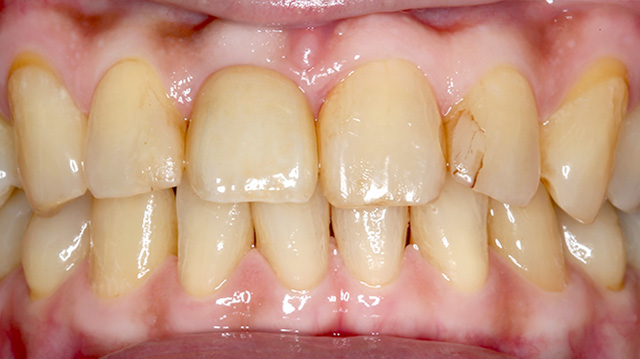

| 年代・性別 | 50代 男性 |

|---|---|

| 主訴 | 転倒して歯が割れた |

| 治療回数 | 3回 |

| 治療期間 | 約1ヶ月 |

| 費用 | 仮歯 5,500円 ジルコニアクラウン 176,000円 |